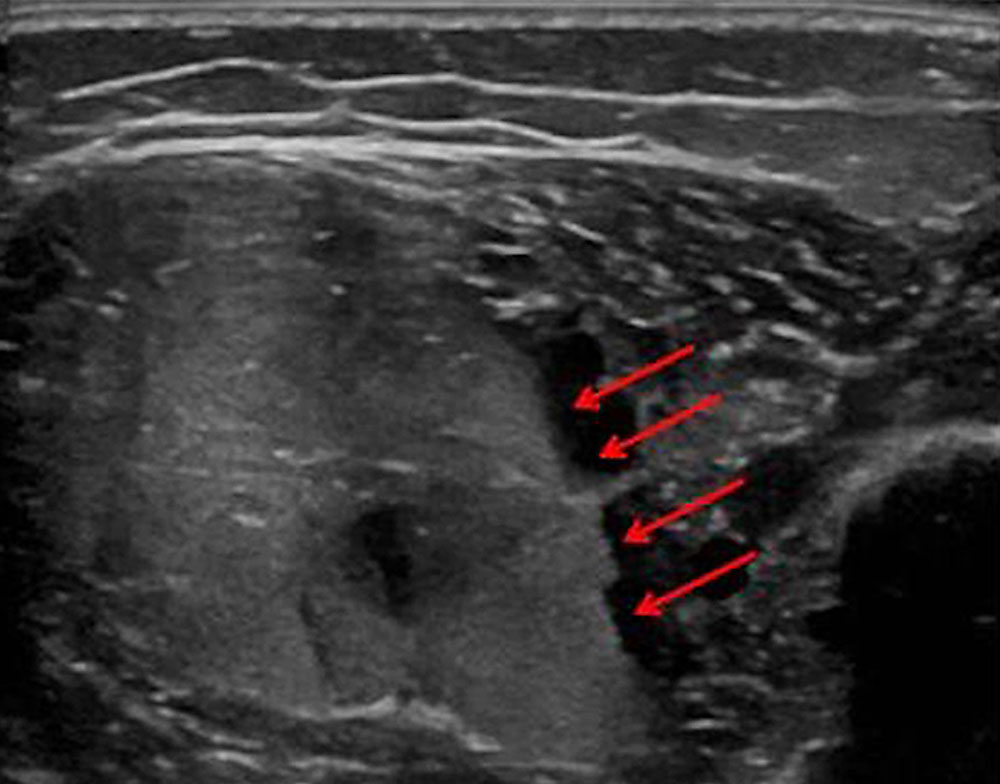

These two types of coagulopathy occur almost exclusively in the clinical pictures of kaposiform hemangioendothelioma / tufted angioma (KHE/TA) as Kasabach-Merritt phenomenon (KMP) and in large-volume venous malformations (VM) as localized intravascular coagulation (LIC), as presented here. The latter can also turn into disseminated intravascular coagulation (DIC) in response to certain triggers such as surgery. Thus, both coagulation phenomena can assume life-threatening severity if inadequately treated or not at all.